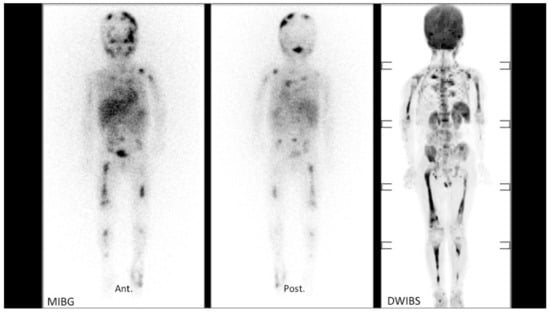

Figure 2 shows an example of a good correlation between 123I-MIBG SPECT scan bone uptake and areas of restricted diffusion on a Coronal 3D MIP reconstructed DWI-MR imaging (DWIBS) for patient #9 (Table 1). These studies were performed before treatment with naxitamab-based chemo-immunotherapy.

Figure 2.

Correlation example of positive bone lesions by 123I-Metaiodobenzylguanidine (MIBG) and diffusion-weighted (DW) Magnetic Resonance Imaging (MRI) for patient #9 (Table 1) before chemo-immunotherapy treatment.

Left (anterior view) and middle (posterior view) panels: positive MIBG in multiple skeleton bones. Right panel: areas of restricted diffusion on a Coronal 3D reconstructed DW-MRI imaging (DWIBS) of the same patient. Note the limitation of skull bone involvement evaluation on DWIBS compared to MIBG.